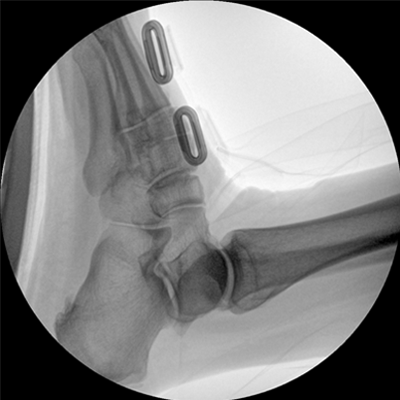

數(shù)字高清影像  助力臨床診斷

專業(yè)的圖像處理系統(tǒng),為您提供高分辨率、高灰階圖像。

Clinical picture

臨床圖片